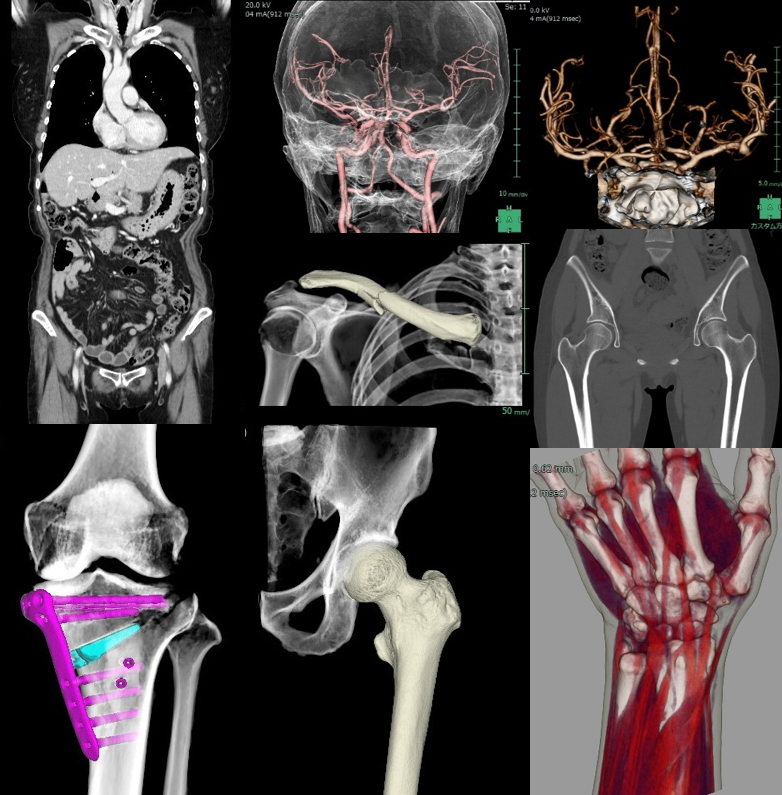

当院では、2025年5月に最新の64列マルチスライスCTを導入しました。CT(Computed Tomography)装置はX線を用いて体の断面を撮影する検査機器で、頭頚部、胸部、腹部、四肢など全身の検査に対応しています。特に、胸部では大動脈や気管支、肺、腹部では肝臓や腎臓などの病変の描出に優れています。当院では、全身領域の検査を実施しており、高度な画像処理により任意の断面や立体的な3D画像を作成することが可能です。そのため、病変の診断だけでなく、手術計画や治療方針の決定にも役立っています。

当院の64列マルチスライスCTは、天井に設置されたAIカメラにより、患者さま一人ひとりに最適なポジショニングを自動で計画し、最も効果的なCT検査を実現します。また、最新のフルデジタル検出器と逐次近似再構成(ASiR-V)を搭載しており、従来のCTと比べて被ばく線量を大幅に低減することが可能です。さらに、目の水晶体など放射線の影響を受けやすい臓器には、正面方向からの直接被ばくを40%軽減するODM(Organ Dose Modulation)機能を備え、安全性にも配慮しています。加えて、従来CTでは体内金属によるアーチファクト(画像の乱れ)が診断の妨げになることがありましたが、SMART MAR(金属アーチファクト低減)機能により、インプラントやクリップ、プレートなどの周囲でもアーチファクトを低減し、より診断能の高い画像を提供できるようになりました。